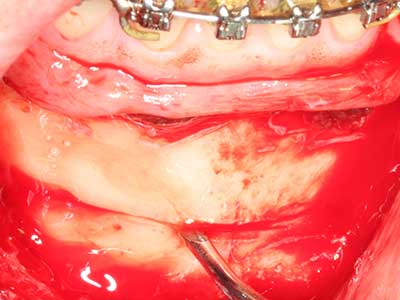

Indication: Autologous bone harvesting

Autologous bone transplants are used in the form of blocks, shells, rings and are also combined with bone replacement materials as chips. If the implant site is prepared at the same time as the augmentation, various bone filter systems have proven effective for collecting the resulting bone chips. As an alternative, the implant site can be prepared using a low-speed device without irrigation. If an implant is not inserted, bone chips can be harvested from the periphery with bone scrapers. This is also possible with piezo surgery using specialized attachments that yield higher-quality bone chips compared chips harvested with round drills, as has been confirmed in a study comparing the two methods (Chiriac, Herten et al. 2005).

Piezo surgery has additional advantages when harvesting bone blocks. In addition to the high precision with osteotomy described above, the use of the thin saw tips specifically minimizes loss of material. Greater loss of material during harvesting can be expected with the thicker instrument tips, particularly when using Lindemann drills (Lakshmiganthan, Gokulanathan et al. 2012). The basal separation, which is necessary particularly for retromolar block transplants, is simplified by specially designed rectangular saws, with the result that piezo surgery is viewed as a precise, simple and safe procedure for harvesting retromolar bone blocks (Happe 2007) (Fig. 1-12).